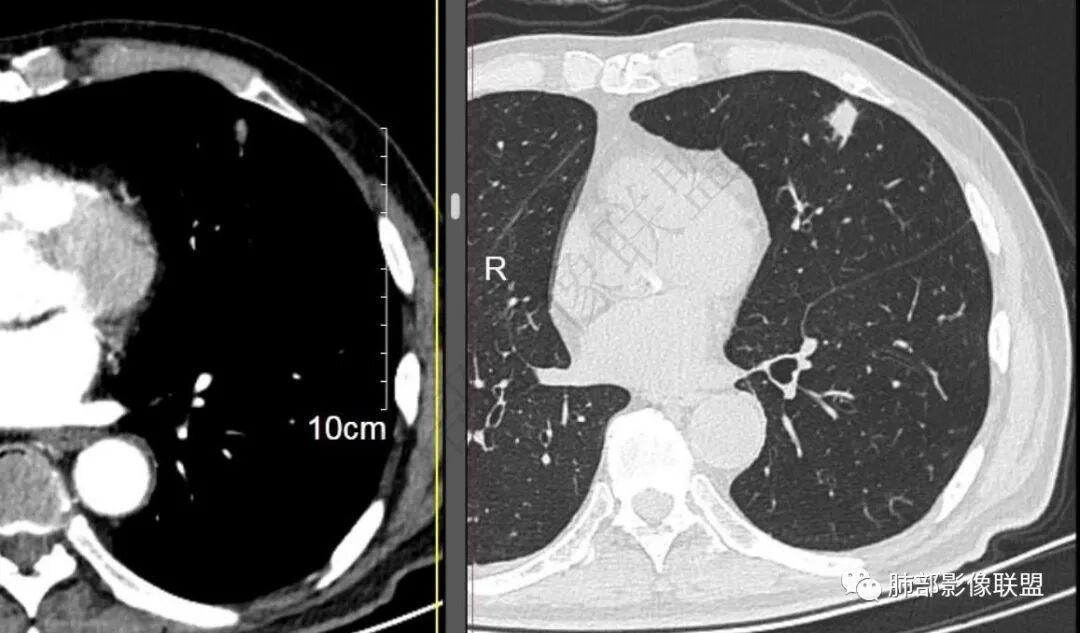

二..发现左肺上叶舌段实性密度小结节影,不规则略呈半环形,边界清楚,未见分叶、毛刺及磨玻璃晕。未见卫星病灶。

9个月后病灶明显增大,边缘较平直,部分膨隆,锁扣样外观,仍旧缺乏典型深分叶及张力,未见胸膜凹陷。

再1个多月后病灶继续增大,较明显不均匀强化,肺门一侧见低密度区。病灶边缘相对不清,可见毛刺。